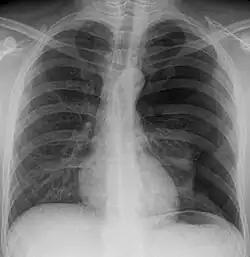

(im Bild rechts)

- Im Thorax-Röntgenbild (Röntgenaufnahme der Lunge) ist ein bedeutsamer Pneumothorax sicher erkennbar.